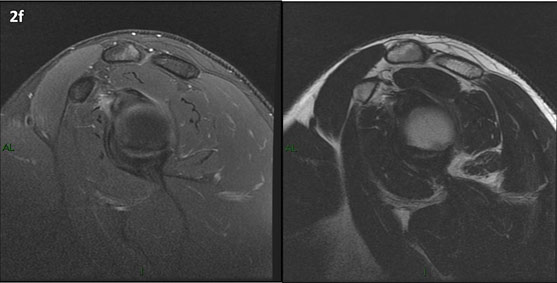

Figura 2 (a-j): Imagens consecutivas de RM no plano sagital nas ponderações T2 com supressão de gordura (DP SG) à esquerda e T2 à direita. Clique na seta para passar as imagens.

Figura 2 (a-j)': Imagens consecutivas de RM no plano sagital nas ponderaçõesT2 com supressão de gordura (DP SG) à esquerda e T2 à direita. Clique na seta para passar as imagens.

Figuras 2b a 2j’: Acompanhando o tendão do redondo menor (seta amarela fina) é possível notar lipossubstituição ao redor da junção miotendínea (setas amarelas grossas) e a atrofia principalmente da porção mais lateral (seta salmão). A porção mais medial (seta branca) tem volume preservado.

Repare que estas alterações também não são evidentes nas imagens com supressão de gordura no plano sagital.

Essa diferença entre os estudos pode ser em parte explicada pelo reconhecimento ou não de que o músculo redondo menor apresenta duas porções anatomicamente distintas e independentes, uma mais superior, que se insere no tubérculo maior, e outra mais inferior, que se insere no colo cirúrgico do úmero, e que a atrofia pode ocorrer em apenas uma delas e passar despercebida.

Chafik et al. também relataram a presença de um pequeno nervo motor acessório em número variável que se insere na porção lateral do músculo redondo menor. O nervo acessório, ao contrário do principal, tem um curso reto e extra-fascial, sendo menos vulnerável aos efeitos compressivos. De fato, nos casos da atrofia parcial do redondo menor, é mais frequente a atrofia da porção mediodorsal com preservação da porção lateroventral, o que poderia ser explicada pela presença do ramo acessório mais lateral do nervo axilar, embora atrofia isolada do componente lateroventral tenha sido reportada em cerca de 17% dos casos de atrofia de apenas uma porção, o que pode ter sido causada por lesão do nervo acessório. No caso do paciente deste mês, a atrofia é mais evidente nesta porção mais lateral e ventral do redondo menor.

É importante que o protocolo de ressonância magnética do ombro tenha sequências ponderadas em T1, T2 ou densidade protônica (DP) sem supressão de gordura em pelo menos dois planos, idealmente nos planos coronal e sagital, para a detecção de lipossubstituição que pode passar despercebida nas imagens com supressão de gordura.